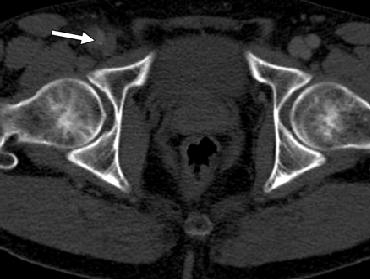

Sự lan của vành bóc tách vào động mạch đùi chung có thể gây ra các dầu hiệu và triệu chứng của thiếu máu chi dưới, với đau lạnh ở ngoại biên, da xanh tái, không có mạch và hoại thư. Vì vậy người ta khuyên khảo sát toàn bộ động mạch chủ và chậu xuống đến bẹn để phát hiện đầy đủ tổn thương (hình 19). Sự lan của bóc tách type B vào các động mạch chậu hoặc đùi có ảnh hưởng đến xử trí và lập kế hoạch làm thủ thuật, đặc biệt khi xem xét đến đặc stent-ghép. Liên quan đến tổn thương động mạch chậu và đùi, nếu xem xét đến việc can thiệp qua da, điều quan trọng là phải xác định có lòng thật để đi vào được hay không với cách tiếp cận động mạch đùi phải hay trái.

Hình 19: Hình axial cho thấy sự lan của vành bóc tách vào đ6ọng mạch đùi chùng phải (mũi tên). Dấu hiệu này nhấn mạnh đến sự cần thiết phải khào sát toàn bộ động mạch chậu và đùi để phát hiện độ lan đầy đủ của tổn thương.